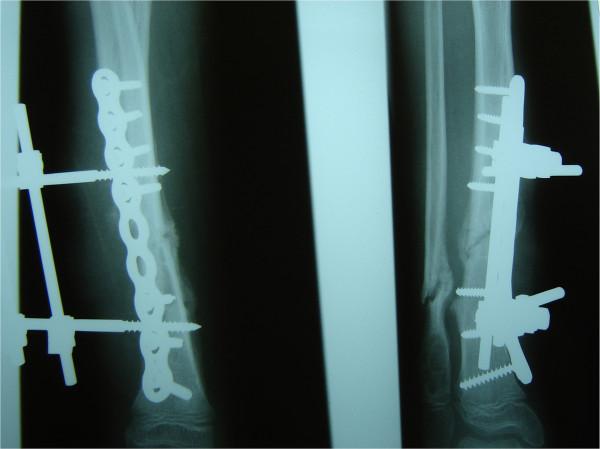

We report a nine-year-old Caucasian girl who had hereditary motor and sensory neuropathy type I and who was admitted with a grade I open tibia fracture after a fall from a small height. Plain radiographs showed a dislocated tibia and fibula fracture. An open reduction with internal fixation with a compression plate osteosynthesis was performed, and soft tissue debridement combined with an external fixateur was undertaken. Three months later, she was re-admitted with localized swelling and signs of a local soft tissue infection in the middle of her tibia. Plain radiographs showed a non-union of the tibia fracture, and microbiological analysis confirmed a wound infection with cefuroxime-sensitive Staphylococcus aureus. Because of the non-union, the osteosynthesis was replaced with an Ilizarov external fixateur, and appropriate antibiotic therapy was initiated. Four months after the initial accident, the fracture was consolidated and we removed the external fixateur.

我们报告一名9岁的白种女孩,她患有I型遗传性运动和感觉神经病变,因从低处跌落导致I级开放性胫骨骨折入院。X线平片显示胫骨和腓骨骨折脱位。进行了切开复位并用加压钢板内固定,同时进行了软组织清创并结合外固定架。三个月后,她再次入院,胫骨中部出现局部肿胀和局部软组织感染迹象。X线平片显示胫骨骨折不愈合,微生物分析证实伤口感染了对头孢呋辛敏感的金黄色葡萄球菌。由于骨折不愈合,将内固定换成了伊里扎洛夫外固定架,并开始了适当的抗生素治疗。初次事故四个月后,骨折愈合,我们拆除了外固定架。